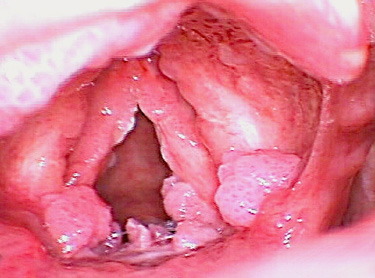

후두유두종이란?

울퉁불퉁하여 사마귀처럼 보이는 양성종양인 유두종은

후두유두종 증상

초기에 쉰 목소리가 나타나며 단발성은 정상 상피가 단순히 이식증식을 일으킨 것이고 다발성 유두종은 소아에게 주로 발생하며 재발이 심하고

넓게 분포가 되어 있으면 호흡곤란증세가 올 수 있습니다.